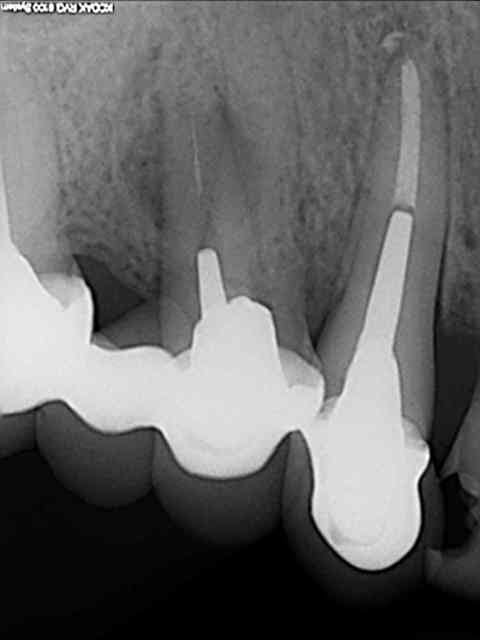

ici , fracture 13-14:

rog avec membrane titane

correction esthétique du niveau des collets de 12 et 11 (forte égression originel de 13-12-11 par rapport au secteur 2)

pose implants

cicatrisation gingivale

mise à jour et aménagement tissulaire type Palacci

modification des collets et des bords libres

prise empreinte

piliers

couronnes...